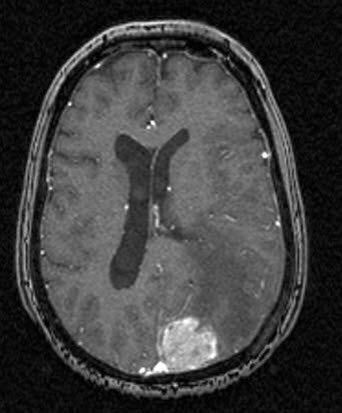

Hjernemetastase, aksialt snitt

Hjernemetastase fra brystkreft

Gjengitt med tillatelse av Radiologisk avdeling, Universitetssykehuset Nord-Norge